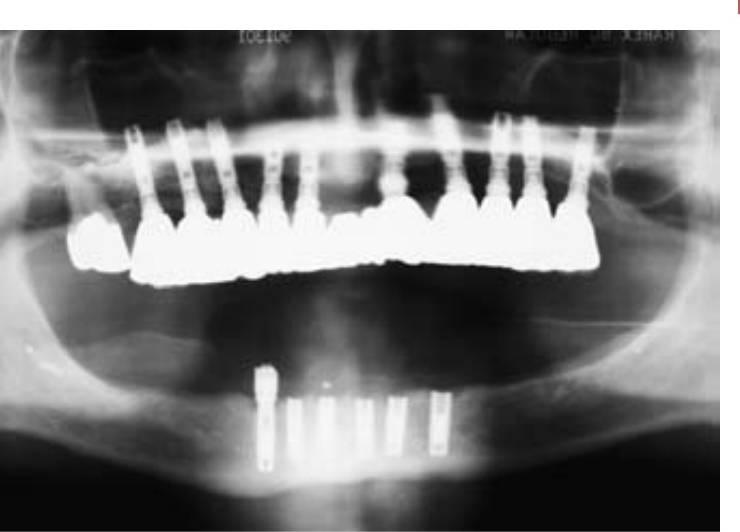

Las complicaciones más comunes relacionadas con los implantes son los problemas biomecánicos que se producen una vez cargado el implante. Un repaso a la literatura referente a los fracasos de implantes indica que estos problemas se producen primariamente durante los 18 meses posteriores a la carga inicial del implante. Estos fracasos iniciales de carga del implante se producen con más frecuencia en los de tipo de hueso más blando (fracaso del 16%) o en los implantes de menor longitud (fracaso del 17%). Estos dos grupos de fracasos están causados típicamente por factores biomecánicos. El hueso blando es demasiado débil para las fuerzas oclusales aplicadas en los implantes, o los implantes más cortos soportan demasiado estrés en la interfase hueso-implante (fig. 4-1).

En algunas ocasiones, un implante puede fracasar poco tiempo después de haberse empezado a «integrar» en el hueso. Antes del fracaso, el implante parece tener una fijación rígida, y todos los indicadores clínicos están dentro de la normalidad. En cualquier caso, una vez que el implante está cargado, se vuelve móvil en el plazo de entre 6 y 18 meses (fig. 4-1). Esto ha sido denominado fracaso temprano por carga por Misch y Jividen. La causa de este fracaso temprano por carga suele ser un estrés excesivo para la interfase hueso-implante. Isidor permitió la integración de ocho implantes en mandíbulas de monos. Las coronas se sujetaban a los implantes cicatrizados con un exceso de contactos oclusales prematuros. Sobre un período de 20 meses, seis de los ocho implantes fracasaron (fig. 4-4). En estos mismos animales, ocho implantes integrados sin cargas oclusales llevaban unas anillas colocadas en el margen gingival para aumentar la retención de placa. Ninguno de estos implantes fracasó a lo largo de los siguientes 20 meses. Los autores concluyeron que en este modelo de animal, el estrés oclusal biomecánico era un mayor factor de riesgo para el fracaso temprano por carga que el componente biológico de la placa bacteriana.

Adell y cols, fueron los primeros en cuantificar y notificar la pérdida de hueso marginal. El estudio indica también la mayor magnitud y aparición de la pérdida de hueso durante el primer año de la carga del implante, con una media de 1,2 mm durante este lapso de tiempo, con un margen de 0 a 3 mm. Este estudio midió la pérdida de hueso desde la primera rosca como línea de base de 0 mm, y no como el nivel original del hueso de la cresta en la inserción, que estaba 1,8 mm por encima de este punto de base. De ahí que la media de pérdida ósea en la cresta durante el primer año sea de 3,3 mm alrededor de los implantes observados (fig. 4-10). Los años siguientes al primero mostraron una media de entre 0,05 a 0,13 mm de pérdida de hueso al año. Otros estudios notificaban una media de pérdida ósea durante el primer año de 0,93 mm, con un margen de entre 0,4 a 1,6 mm y una media de pérdida de 0,1 mm después del primer año. La pérdida inicial del hueso de la cresta se ha observado con tanta frecuencia que el criterio propuesto para el éxito de los implantes no suele incluir siquiera la cantidad de pérdida ósea durante el primer año.